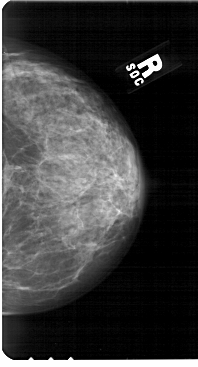

A_1851_1.RIGHT_MLO

RIGHT_MLO LINES 5491 PIXELS_PER_LINE 3091 BITS_PER_PIXEL 12 RESOLUTION 43.5 NON_OVERLAY

RIGHT_CC LINES 5491 PIXELS_PER_LINE 2956 BITS_PER_PIXEL 12 RESOLUTION 43.5 NON_OVERLAY